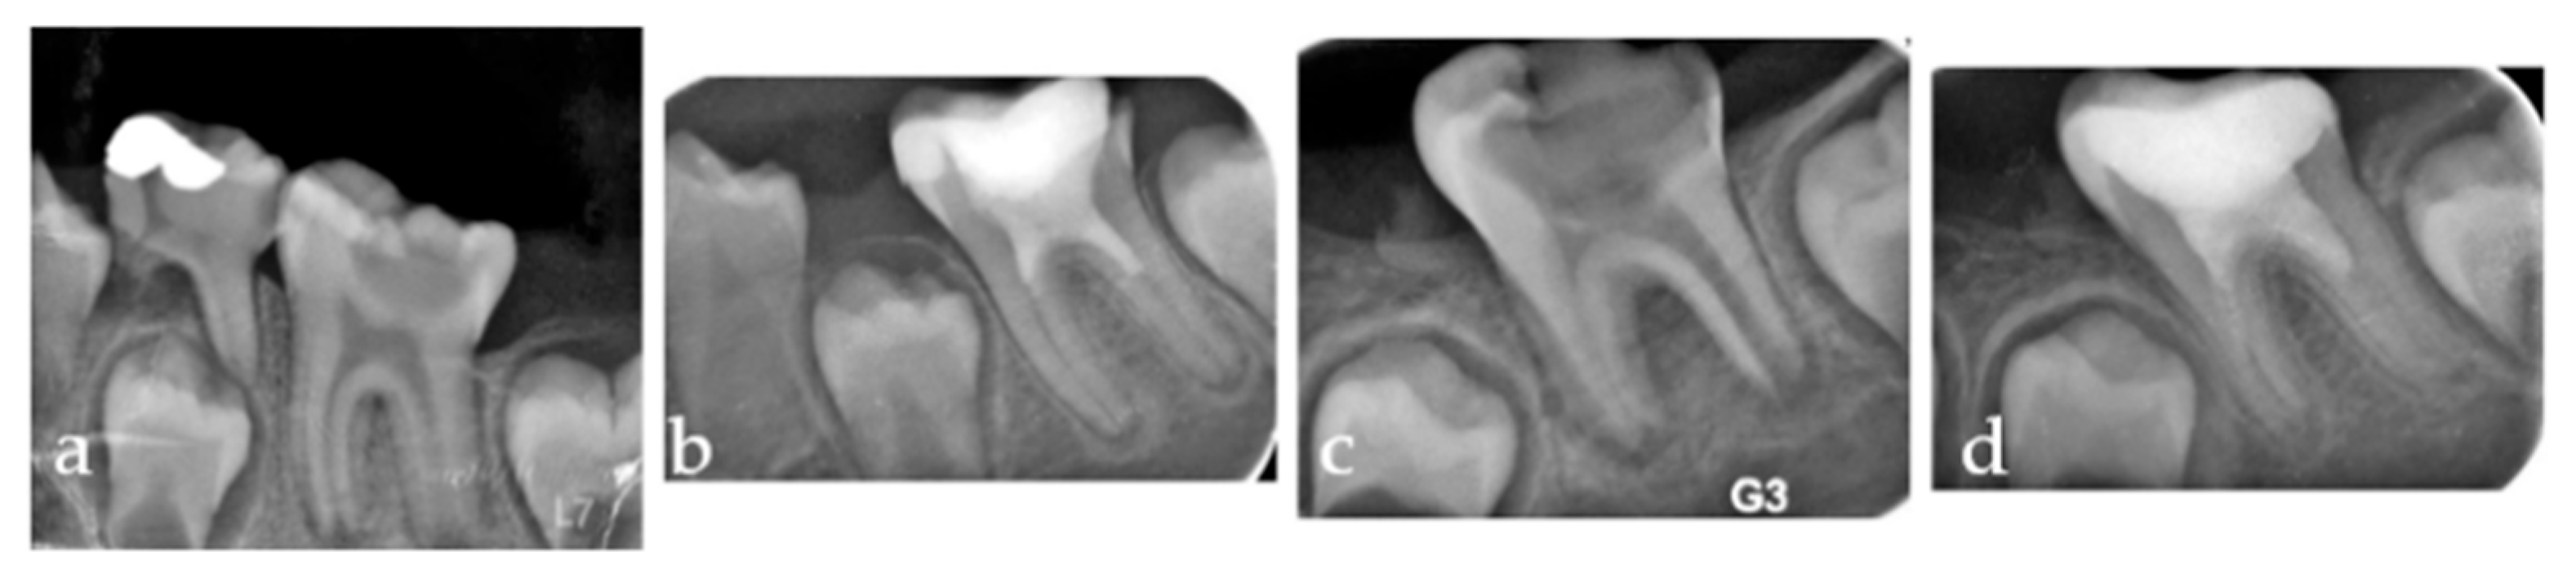

A corresponding ROI of equivalent dimensions was precisely positioned at the symmetrical contralateral site, serving as an internal control. ROI placement was performed with meticulous care to avoid interfering with anatomical structures, such as the mandibular canal and developing tooth germs. To further enhance consistency and precision, images were rotated and magnified as necessary before ROI selection. Each ROI was subsequently cropped and duplicated. A Gaussian blur (σ = 35 pixels) was applied to the duplicate image to suppress variations attributed to soft tissue. The blurred image was then subtracted from the original to enhance the contrast of trabecular structures, followed by the addition of a constant grayscale value (128). The resulting image was then binarized into a black-and-white format. Subsequent noise reduction was achieved through the sequential application of “erode” and “dilate” operations. The processed images were then inverted and skeletonized to enable a detailed visualization of the trabecular structure (Figure 3). FD was calculated using the “Fractal Box Count” plugin within ImageJ, employing a range of grid sizes (2, 3, 4, 6, 8, 12, 16, 32, and 64 pixels). The number of occupied boxes was plotted against box size on a double-logarithmic graph, with the slope of the regression line interpreted as the FD (Figure 4). All analyses were conducted independently for both the treated and control sites to ensure internal validity.

Figure 3. (a) Cropped image of the relevant area; (b) Duplicated image; (c) Application of Gaussian filter; (d) Image subtracted from the original; (e) Grayscale adjustment; (f) Binarization; (g) Erosion; (h) Dilation; (i) Inversion; (j) Skeletonization.